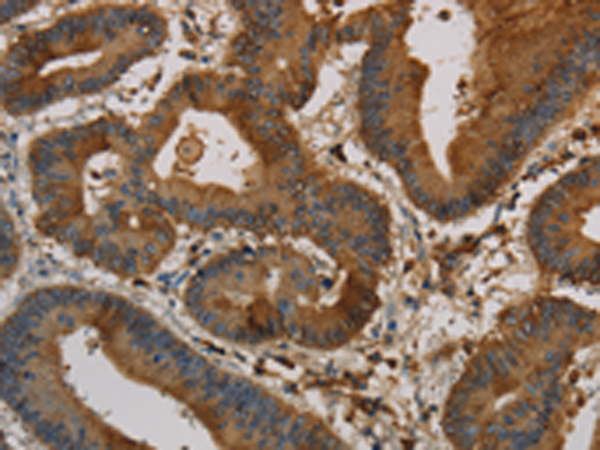

分类: 科研抗体货号: P10762别名: MDL1; MDL-1; CLECSF5应用: IHC反应种属: Human